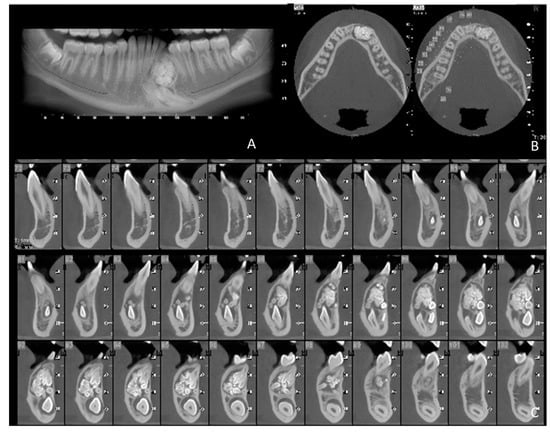

1.3. Case Number 3